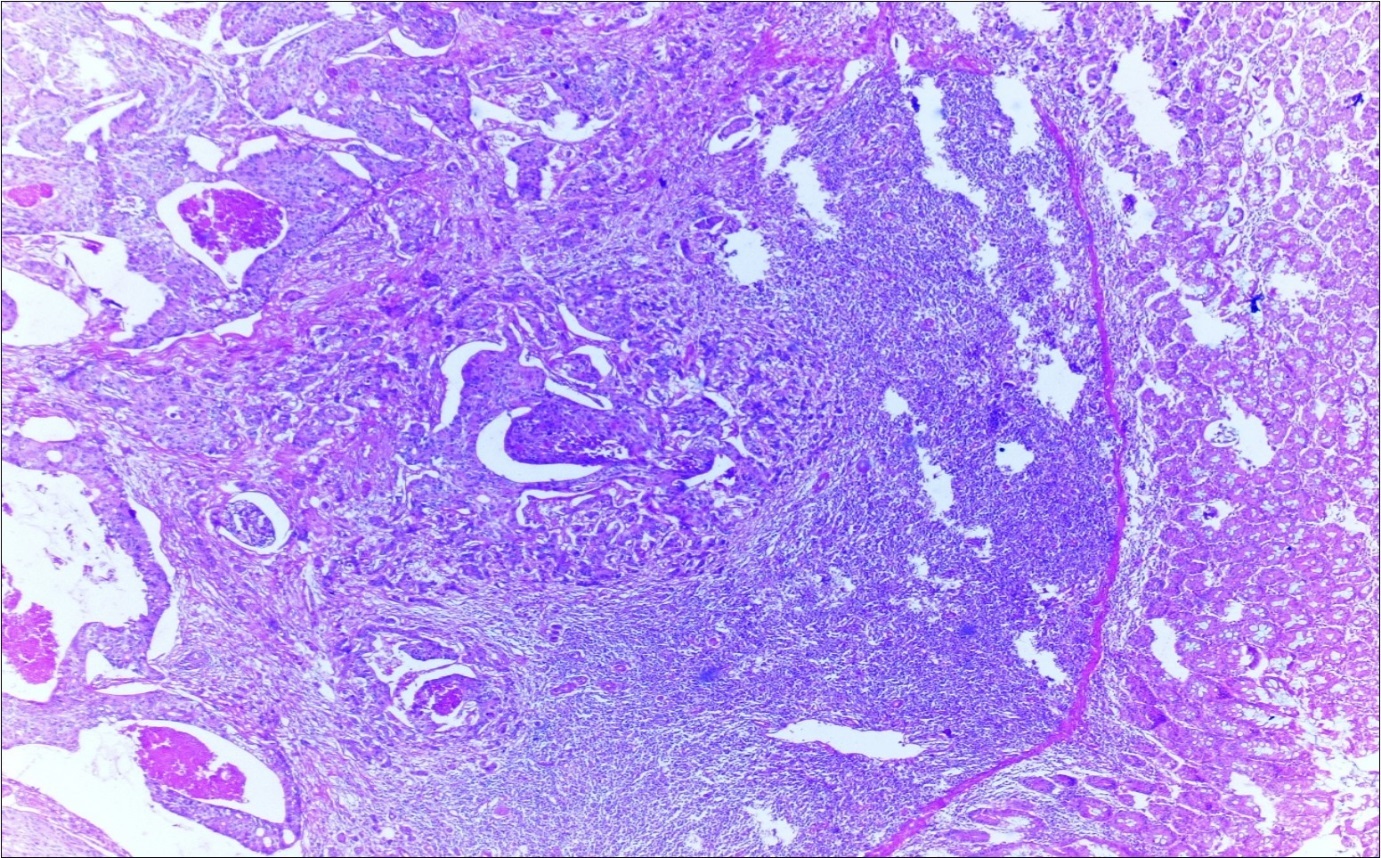

A 63-year-old woman presented to the Department of General Surgery as an outpatient with abdominal pain. Physical examination showed the signs of acute appendicitis and appendectomy was performed. During microscopic examination, a small focus of atypical monotonous lymphoid cell population was seen and the material was sampled totally. The pathological examination revealed MALT lymphoma (Figure 1), with diffuse positivity of cluster of differentiation (CD) 20 (Figure 2), CD 79a and B-cell lymphoma (Bcl- 2) (Figure 3) with just a few CD3 positive lymphoid cells. However, no evidence of adenocarcinoma was found in the appendectomy specimen. After the diagnosis of lymphoma, a complete colonoscopy was planned and this revealed a solid tumoral mass in the caecum measuring 5x4x4 cm. Computed tomography of the abdomen and pelvis revealed mesenteric lymphadenopathy associated with a mass in the caecum with multiple nodules in liver consistent with metastasis (Figure 4). Frozen sections were not obtained since the treatment method would not be affected. The patient underwent anterior resection with regional lymphadenectomy, with the pathological assessment of the resected specimen revealing a collision tumor consisting of a poorly differentiated adenocarcinoma extending through the muscularis propria with MALT lymphoma (Figure 5). Microscopic evaluation of the 11 regional lymph nodes in the mesentery of the resected colon and liver biopsy showed diffuse infiltration of MALT lymphoma with metastasis of adenocarcinoma (Figure 6). According to immunohistochemistry, atypical lymphocytes were positive for CD 20, Bcl-2, and negative for CD3, CD5, CD10, CD23, Bcl-6, terminal deoxynucleotidyl transferase, and cyclin D1. The proliferation fraction (MIB-1 immunostaining) was approximately 20%. The morphological and immunohistochemical findings were used to confirm the diagnosis of synchronous presentation of MALT lymphoma and colon adenocarcinoma within the caecum, mesenteric lymph nodes and liver metastases.

Figure 4.Adenocarcinoma with MALT lymphoma infiltration of liver (h&e;200)

Adenocarcinoma with MALT lymphoma infiltration of liver (h&e;200)